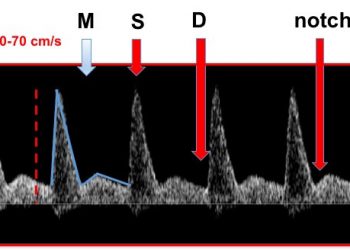

How To Do Giugno 2020: le arterie uterine

Finalmente on line il nuovo video "How to do" del mese di Giugno, sul campionamento delle arterie uterine! Grazie a...